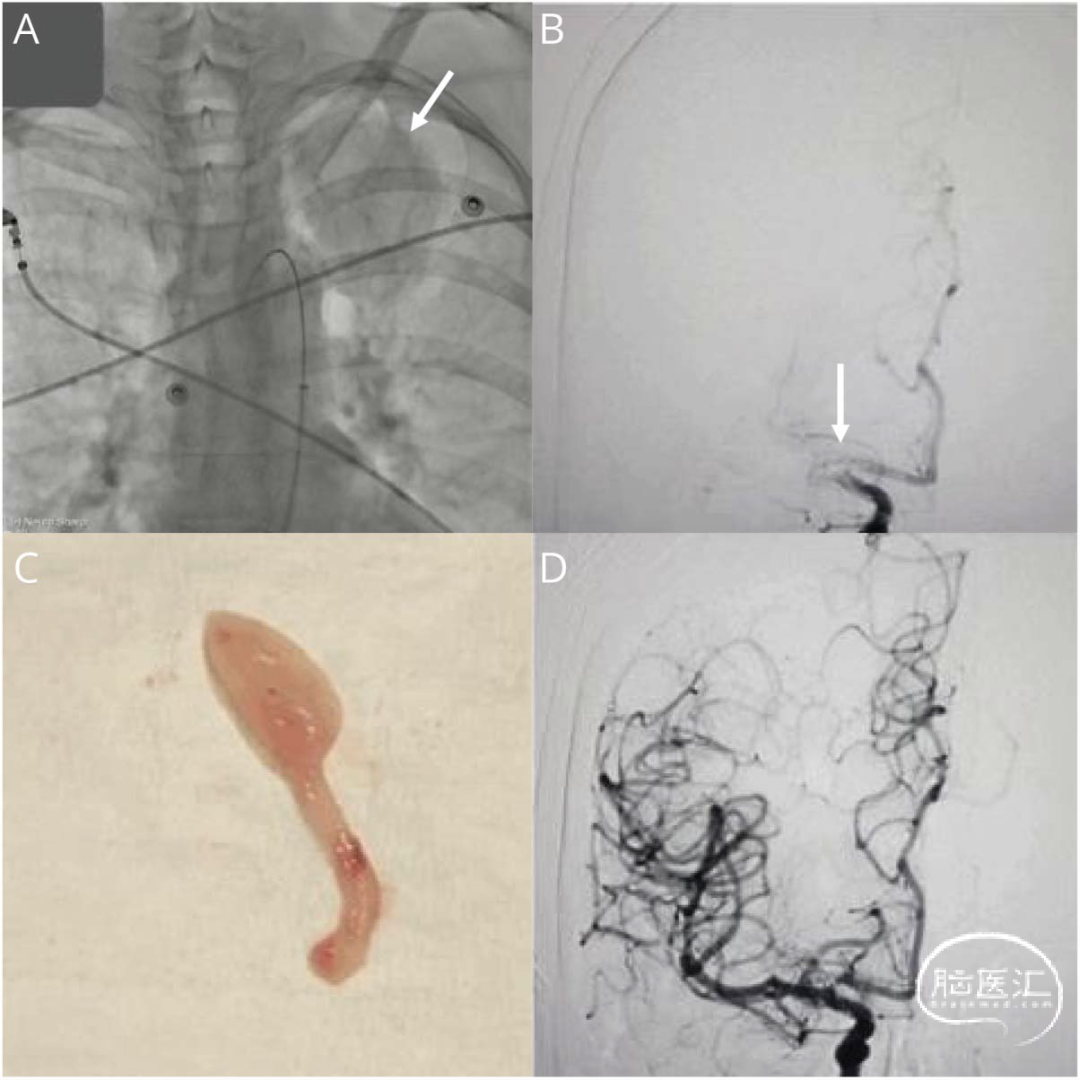

CTA显示右大脑中动脉近端闭塞。给予静脉注射替萘普酶治疗,并进行紧急血管内治疗。血管造影期间,发现左肺尖肿块(图1.A)。抽吸取栓成功复通取出的血栓为米色和凝胶状(图1.C)。脑磁共振成像显示右基底节梗死面积小,无脑转移。

栓子的病理学显示分化较差的恶性肿瘤,可能是癌症(图2)。